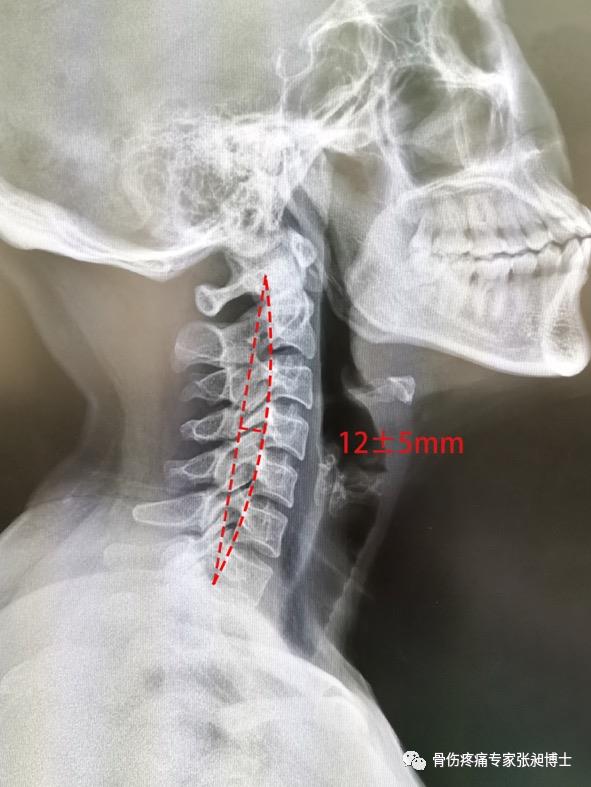

图1-1-2 颈椎的正常生理曲度

在颈椎X线的侧位片上,沿枢椎的齿状突后缘最高点与第七颈椎后下缘作一直线,将颈椎椎体后缘连一弧线。直线与弧线之间最宽处的距离正常值为12mm±5mm。